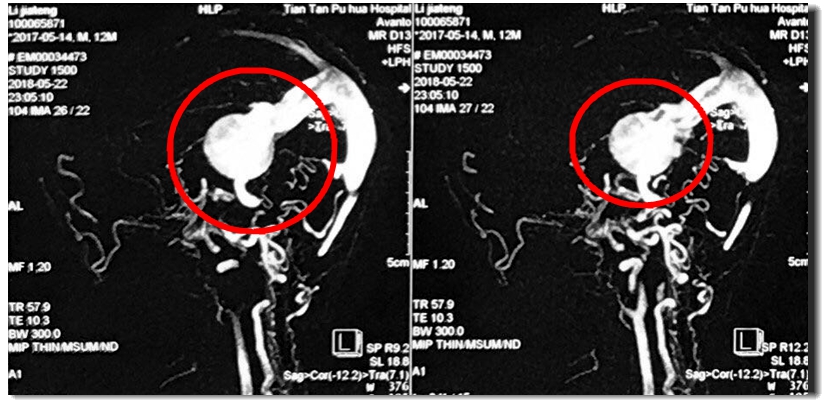

这是手术前后的造影图。可以看出来,术前血液都跑到两个大球里,大脑供血几乎看不到。而术后,大黑球消失,瘤子所处的大脑区域有了明显的血液供应,枝杈丰富,几乎能听见血液在此前干瘪的血管中欢快地奔腾。